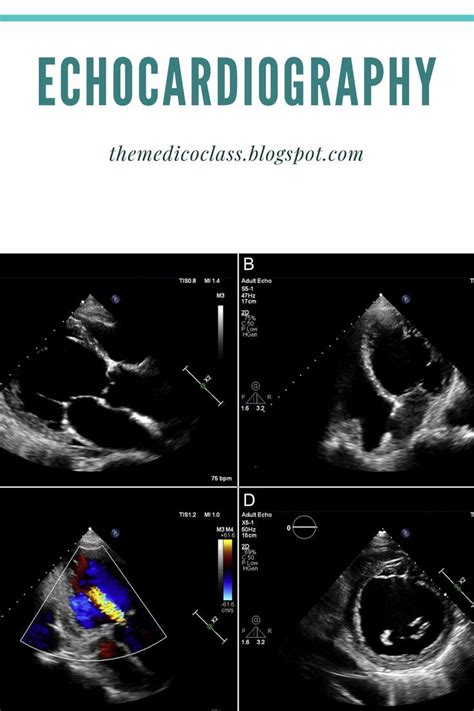

Echocardiography Views Explained

Hey guys! Ever wondered what all those different angles and pictures mean during an echocardiogram? You’re in the right place! We’re diving deep into the fascinating world of echocardiography views , breaking down what they are, why they’re super important, and how they help doctors get a crystal-clear picture of your heart. Think of these views as different windows into your heart’s incredible engine, each offering a unique perspective to help diagnose and manage heart conditions. Whether you’re a medical student, a curious patient, or just someone who likes to understand their health better, this guide will illuminate the essential echocardiographic views you need to know. We’ll cover the standard views, what they show us, and why they’re the bedrock of cardiac ultrasound interpretation. So, grab a coffee, get comfy, and let’s start exploring the amazing insights these views provide!

Now, let’s get into the nitty-gritty of the most commonly used views, especially in a transthoracic echocardiogram (TTE), which is the standard ultrasound done from outside your chest. These views are the bread and butter for most cardiac assessments. We’ll break them down one by one, focusing on what you see and why it’s important. Think of these as your essential checklist for understanding a basic echo report.